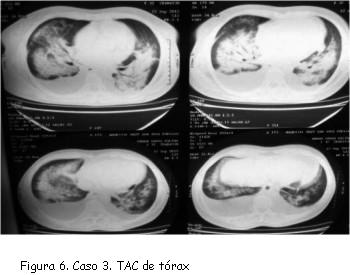

TAC de tórax simple: infiltrado retículo alveolar en ambos campos pulmonares, el cual tiene distribución en alas de mariposa. Derrame pleural bilateral de predominio derecho. Cavidades cardíacas de características normales (figura 6).